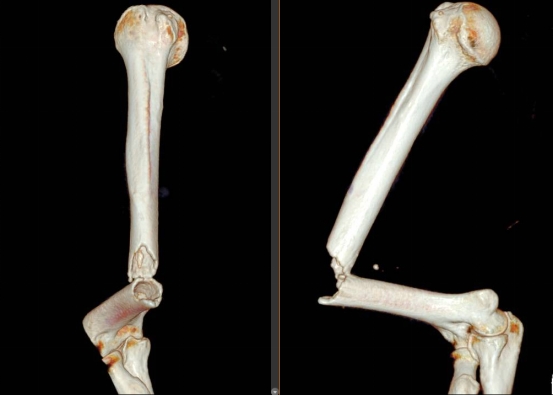

术前三维重建